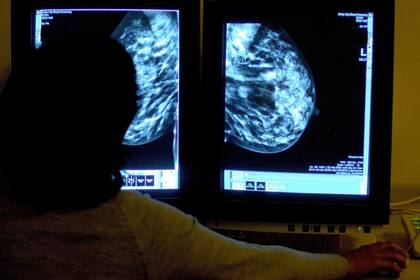

Existe una sola forma efectiva de detectar a tiempo el cáncer de mama: la mamografía, un examen médico no invasivo. En general, se recomienda una mamografía anual a partir de los 40 años a todas aquellas personas asintomáticas. Sin embargo, en las pacientes con antecedentes de cáncer de mama en familiares de 1° grado (madre, hermana) se recomienda realizarla 10 años antes de la edad de detección del cáncer del familiar más cercano.